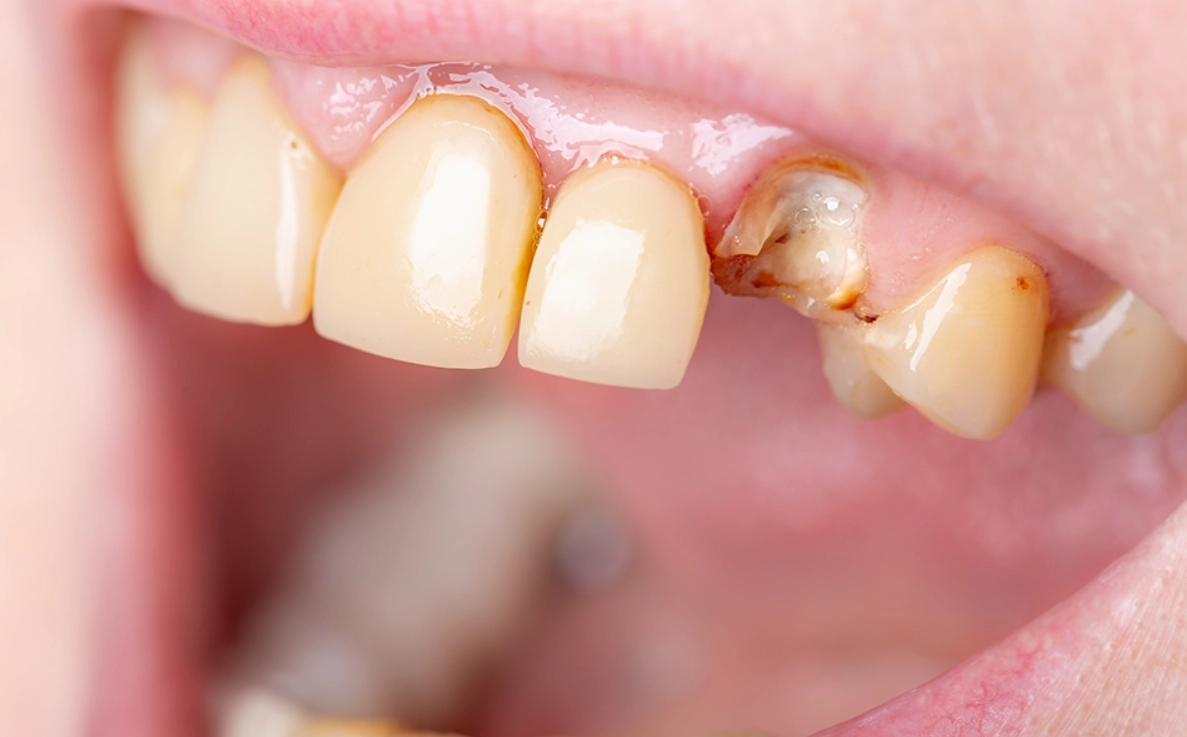

對,就是字面意思。排除生理原因永遠是第一步。夜間磨牙(學名:睡眠磨牙症)是導致牙齒斷裂的常見原因,而壓力正是磨牙的主要觸發因子之一。你可能完全沒意識到自己正在磨牙。

去看牙醫時,可以主動告知:「我最近夢到牙齒斷掉,有點擔心,可以請您幫我檢查是否有磨牙跡象或牙齒有隱裂嗎?」專業的牙醫能從琺瑯質磨損狀況判斷。如果真有磨牙問題,一副量身訂製的夜間牙套,既能保護你的牙齒,也從物理上中斷了「壓力→磨牙→夢到牙壞→更焦慮」的惡性循環。這是一個非常實際的自我照顧行動。